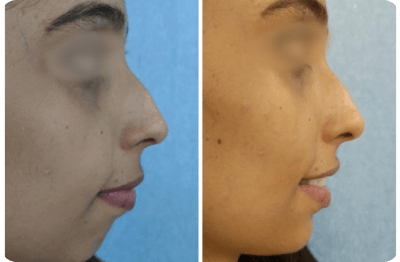

Maxillofacial Harmonization

Maxillofacial harmonization enhances facial balance non-surgically by addressing jaw size, position, and asymmetries.